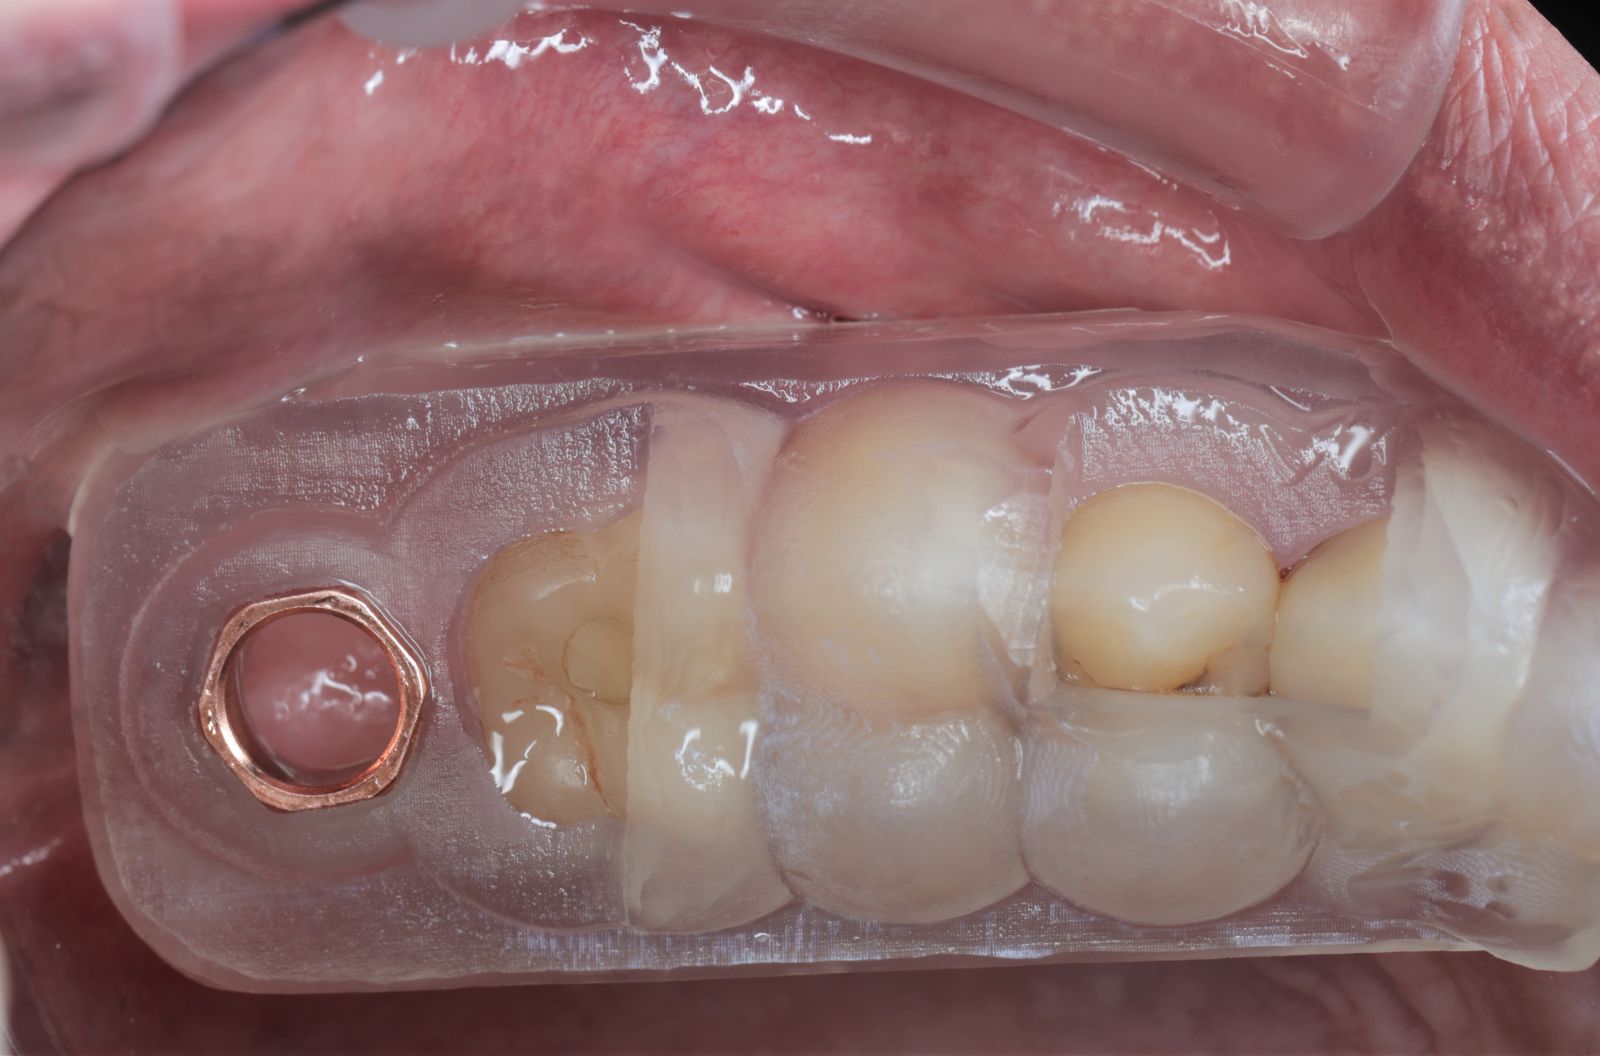

- 手術過程使用3D列印的高精準度導引板,不只增加手術的穩定性、安全性,減小手術傷口,減少疼痛,讓術後傷口復原時間更短,不影響日常生活及工作。

【 案 例 三 】

- 手術過程,在植入植體前先用導板定位,確認植牙位置及角度。使用導板讓傷口範圍縮小。

- 手術後傷口小無需縫合,也不用再來拆線,幾乎不會腫脹出血,術後恢復期舒適快速!